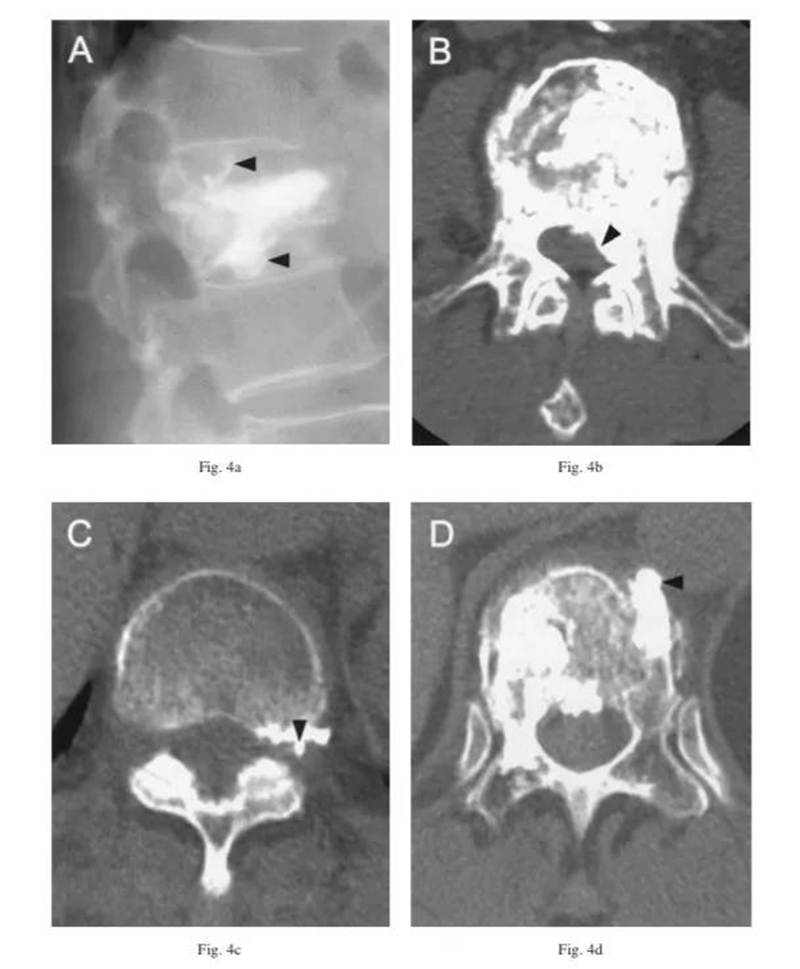

根据渗漏的途径及CT表现,将骨水泥渗漏分为三种类型:B经椎旁静脉渗漏;S经节段血管渗漏;C经皮质缺损渗漏。

B经椎旁静脉渗漏:在椎体后缘相对对称分布。一般不超过椎管横径的1/3。矢状位CT显示会向头尾侧弥散。

S经节段血管渗漏:沿节段静脉走行弥散。轴位CT呈水平走行。有时会顺着血管上下弥散,矢状面呈垂直或斜行。

C经皮质缺损渗漏:顺着缺损区到处跑,椎体周围、椎管内、椎间盘,哪里有路往哪走。